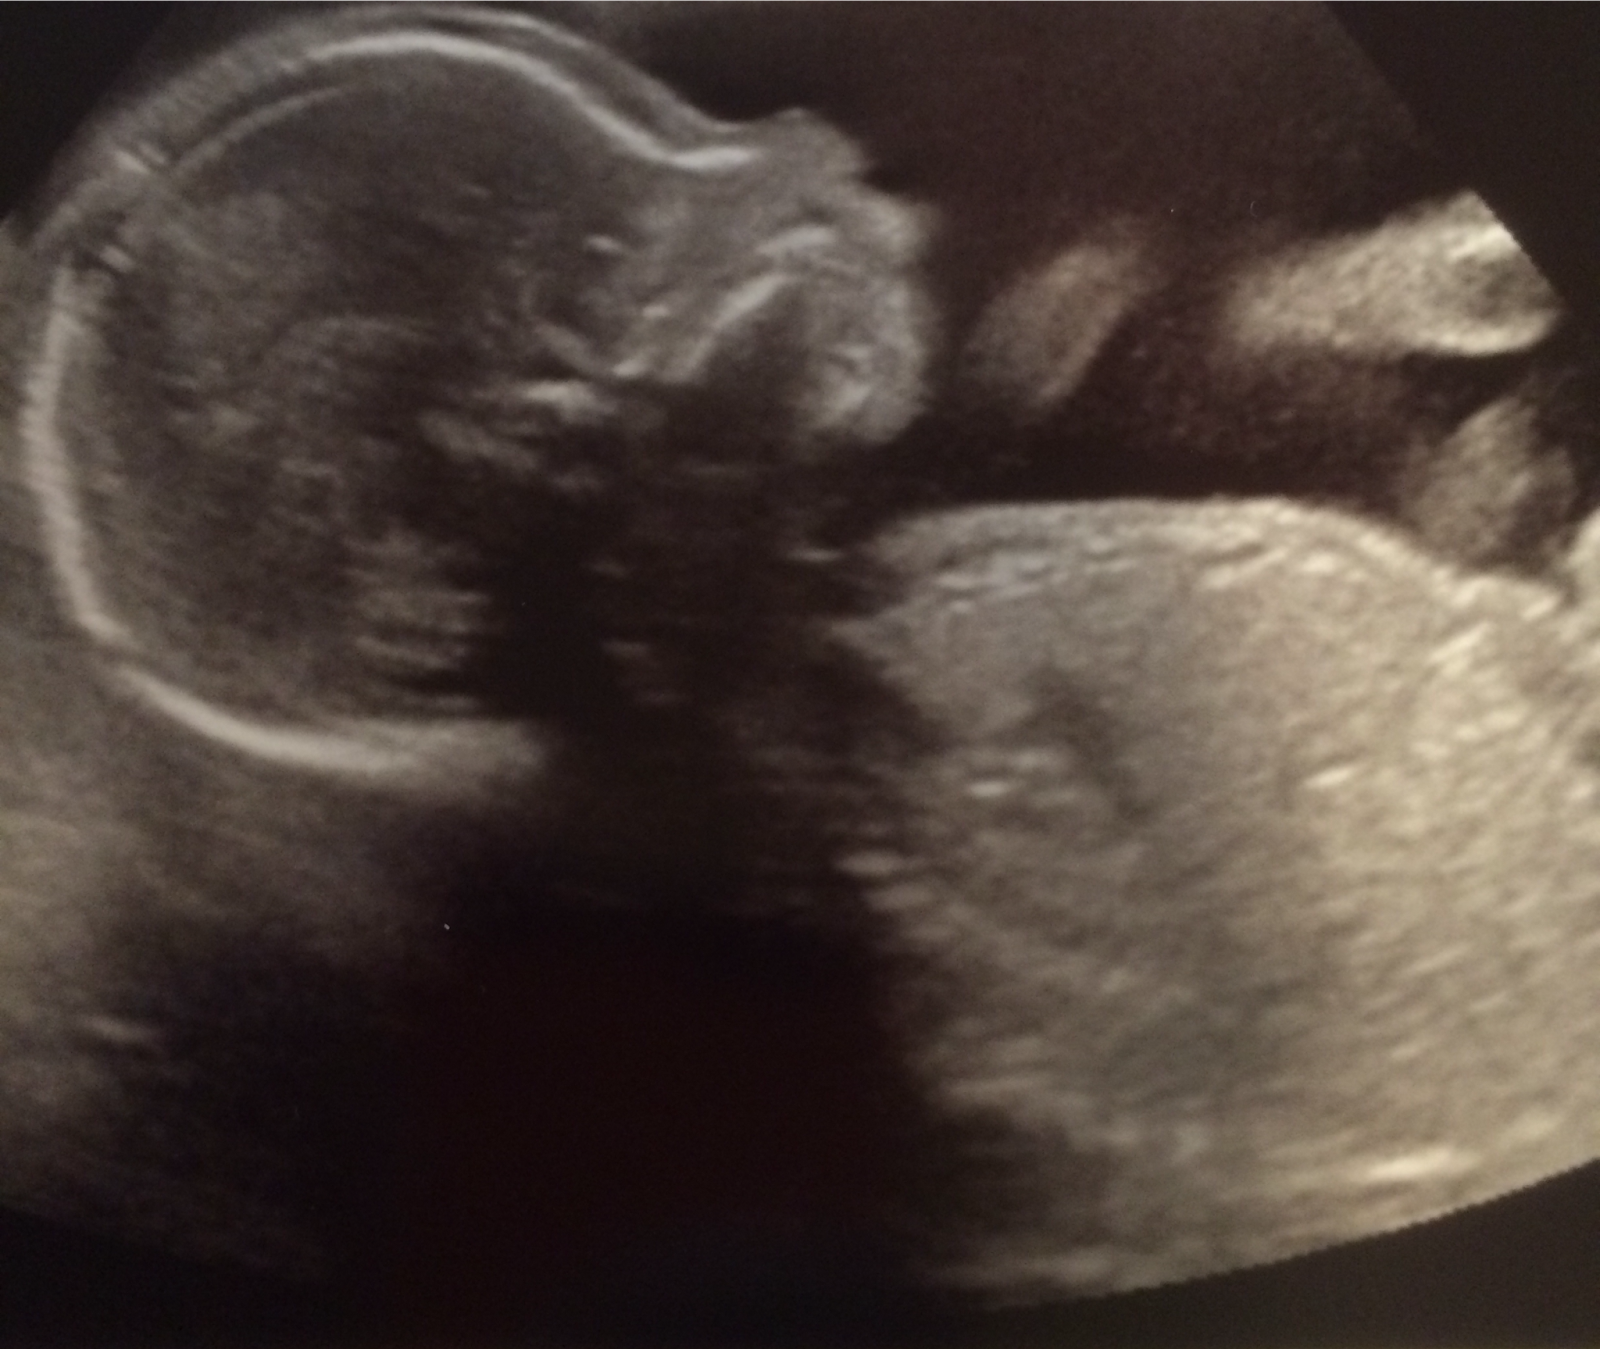

In honor of American Heart Month, we wanted to update everyone about the pregnancy. As most of you probably know by now we are having a boy, Alexander Steven. At the same ultrasound that we found out we'd have another little boy running around, we also learned that he has something wrong with his heart. We have come a long way since then and have learned a lot. Alexander has what is called Tetralogy of Fallot with Pulmonary Atresia and will require open heart surgery after he is born. We are lucky enough to be so close to CHOP which is where Erica will deliver and where Alexander will have his surgery. So far, he is growing well and the doctors are very happy with how well his heart is growing. The doctors at CHOP are some of the best in the world, and we are so happy to have them caring for Alexander.